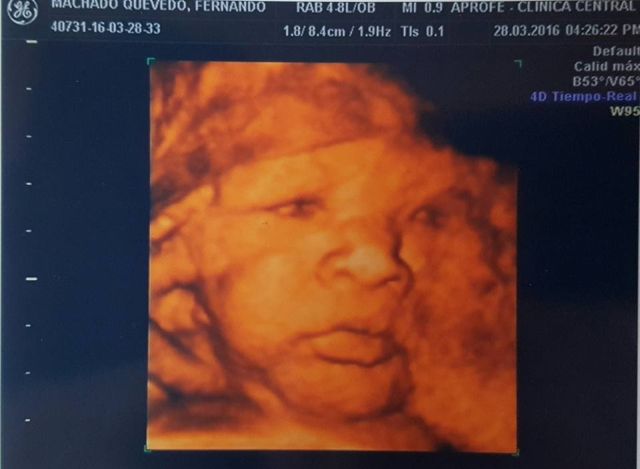

Peste numai o lună, cei doi vor avea un băiețel și numără zilele până la momentul cel mare. Fernando a postat pe pagina ei de socializare o fotografie cu ecografia micuțului.